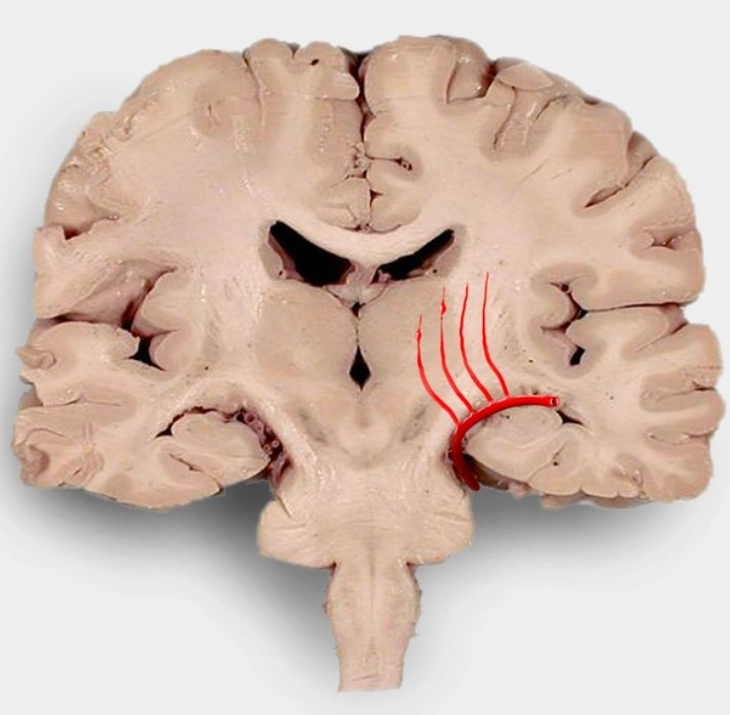

Xuất huyết Duret (Duret hemorrhages)

16/03/2026